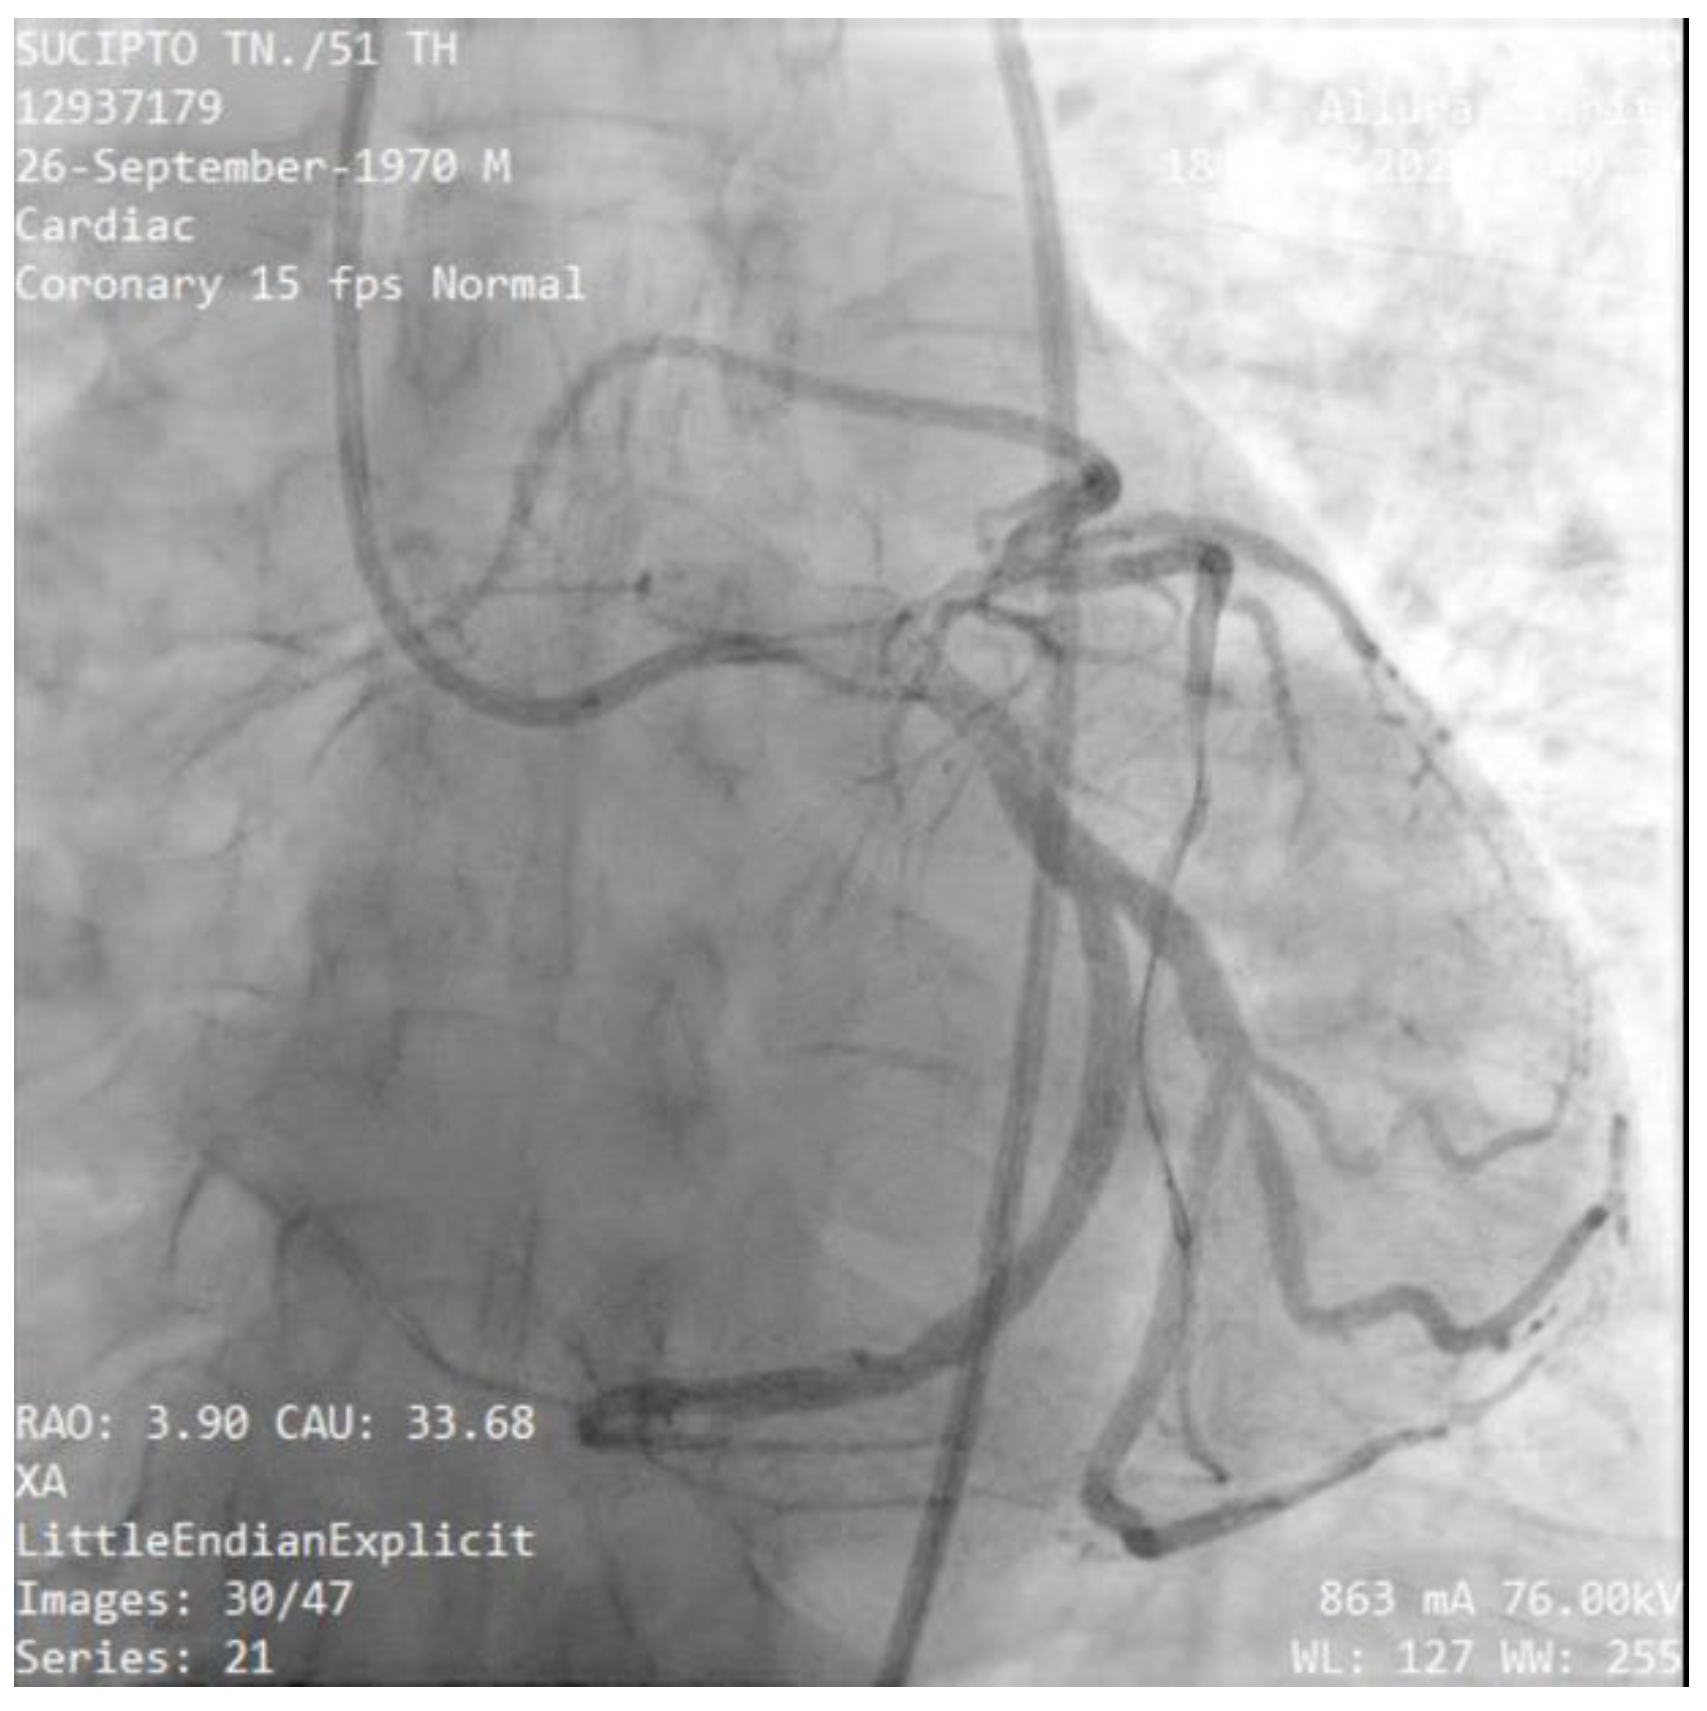

A 53-year-old male was referred from a local tertiary hospital with a chief complaint of sudden, typical chest pain with a 6-hour onset, accompanied by complaints of nausea and vomiting numerous times. The patient's medical history was lacking. Physical examination revealed he was hemodynamically unstable, with a blood pressure of 90/60 mmHg, 60 beat per minute with irregular pulse and mild tachypnea of 22 breaths per minute. Electrocardiogram (ECG) examination revealed a paroxysmal slow atrial fibrillation rhythm of 40–75 beats per minute (Figure 1), which changed 2 hours later to total AV-Block (TAVB) dan show ST-segment elevation (STEMI) in the inferior lead and horizontal ST depression in leads V1–V4 (Figure 2). The patient then underwent primary PCI in the cath-lab and temporary pacemaker implantation. At the time of angiography, the attempt to engage in the right coronary artery (RCA) ostium failed, which suspected an RCA anomaly (Figure 3). Then we tried guiding through the left main coronary artery (LMCA) to the left circumflex artery (LCx), found total occlusion in the mid-left circumflex, and long lesions in the ostium to the proximal left anterior descending artery (LAD). We decided to open the total occlusion that occurred in the LCx, as soon as the LCx was opened there was ostium of the RCA (Figure 4). A total occlusion was successfully opened, and a stent was placed on the coronary culprit (mid-LCx), with the final result being good to distal flow (TIMI flow III). The patient was then sent to the critical care unit for close hemodynamic observation and received optimal medical treatment, including antiplatelet therapy (aspirin and ticagrelor), high-intensity statin (atorvastatin 40 mg/d). The patient was discharged two days later after undergoing general treatment and it has been confirmed that there are no acute complications of right heart failure.

Figure 4. Case 1#: The ostium of RCA originates from the LCx.